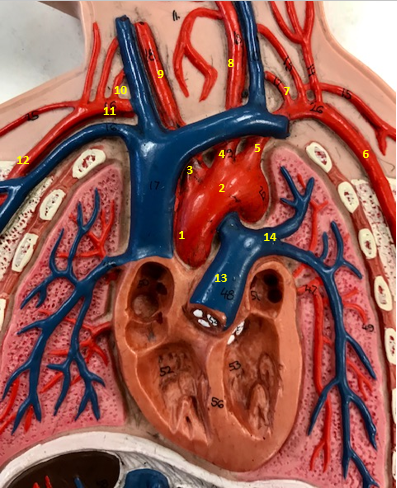

Aorta

Name #2

Brings blood out of left ventricle

Function of aorta

Brachiocephalic artery

Name #3

Supplies oxygenated blood to right arm shoulder neck and head

Function of brachiocephalic artery

Left common carotid artery

Name #4

Supplies oxygenated blood to left neck and head

Function of left common carotid artery

Left subclavian artery

Name #5

Supplies oxygenated blood to left arm shoulder

Function of left subclavian artery

Left axillery artery

Name #6

supplies blood to left armpit and upper limb

Function left axillary artery (6)

Left vertebral artery

Name #7

Supplies blood to brain and spinal cord

Function of left vertebral artery (7)

Left common carotid artery

Name #8

Supplies blood to left neck and head

Function of left common carotid artery (8)

Right common carotid artery

Name #9

Supplies oxygenated blood to right neck and head

Function of right common carotid artery (9)

Right vertebral artery

Name #10

Supplies blood to brain and spinal cord

Function of right vertebral artery (10)

Right subclavian artery

Name #11

Supplies blood to right arm and shoulder

Function of right subclavian artery

Right axillery artery

Name #12

Supplies blood to right armpit and upper limb

Function of right axillery artery (12)

Pulmonary trunk

Name #13

Bring blood out of right ventricle to lungs

Function of pulmonary trunk (13)

Left pulmonary artery

Name #14

Bring blood to left lung

Function of left pulmonary artery (14)